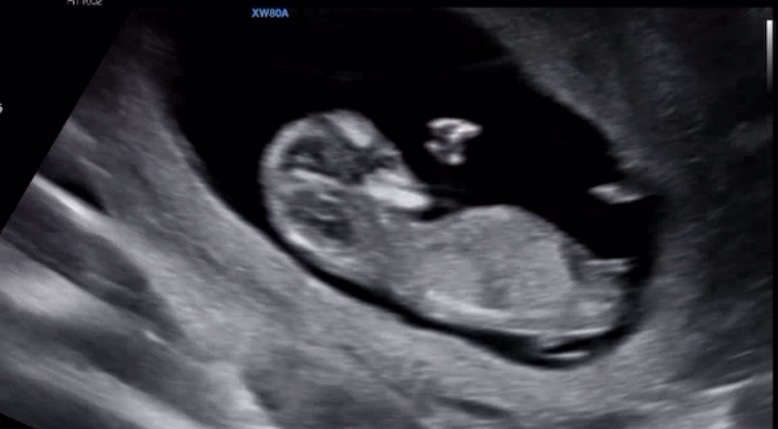

11주 5일 각도법 투표해주세요~

베이비빌리ai는 아들이라고 하고 지피티는 딸이라네요! 투표해주심 감사해용❤️